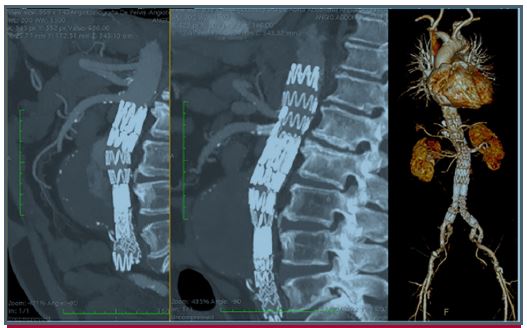

Endoleak tipo 2 “maligno”: una entidad ya conocida, pero con un comportamiento más agresivo